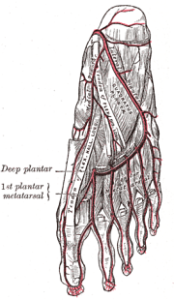

El músculo oponente del quinto dedo del pie recibe irrigación de la arteria plantar lateral o lateral externa, que se origina de la tibial posterior. Esta arteria es de suma importancia en la nutrición de los músculos y huesos de la planta, así como de los dedos del pie.